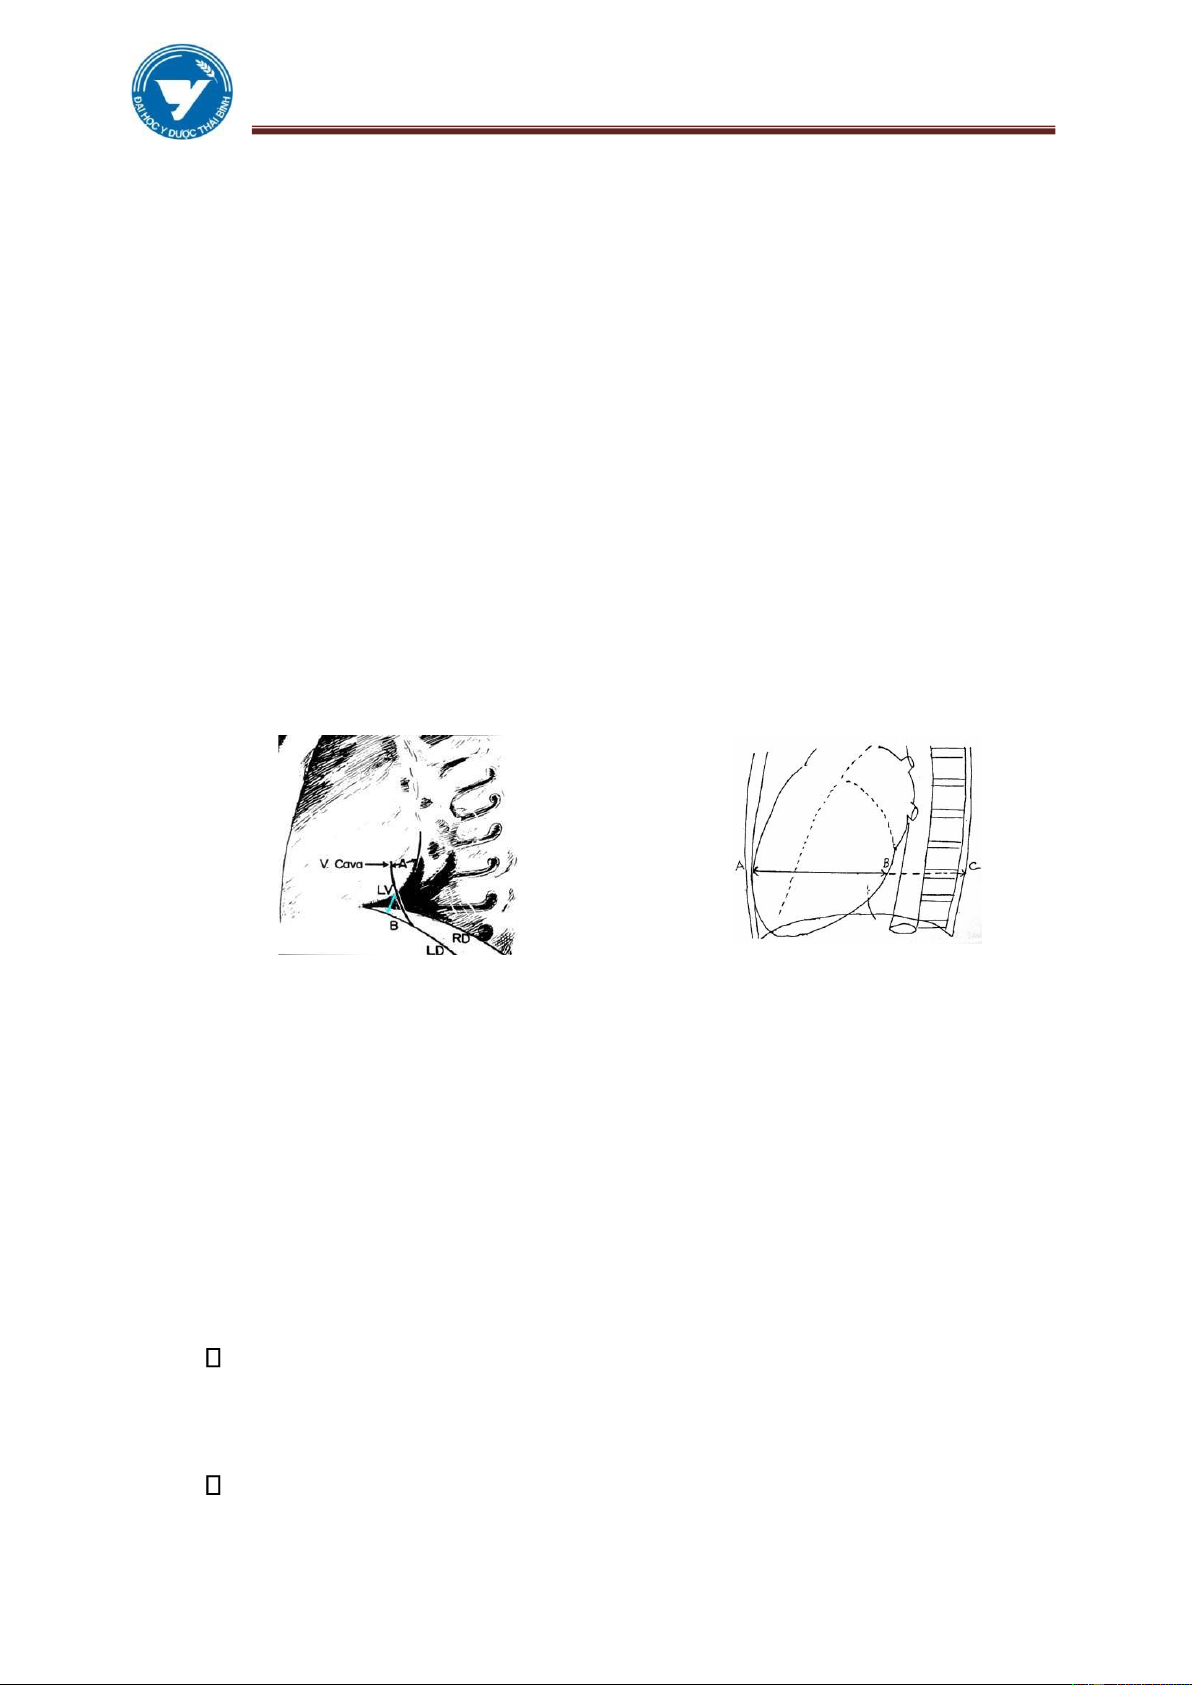

Hình 3.1: Các bờ và các cung tim tư thế

Hình 3.2: Các bờ và các cung tim tư thế thẳng nghiêng trái

1.3. Các đường kính của tim Đường kính dọc L:

Đường kính từ D → G’ là đường kính trục xuyên từ đáy đến đỉnh của tim (L ≈

13 - 14 cm). L nói lên sự tương quan của tim với lồng ngực và ổ bụng.

✓ L làm một góc α với đường thẳng đứng.

✓ Ở người bình thường α # 45o.

✓ Ở người gầy cao α < 45o.

✓ Ở phụ nữ mập thấp α >45o.

Hình 3.5: Các đường kính của tim Đường kính đáy B

Là đường D’G, đáy của tim chủ yếu là 2 nhĩ (B ≈ 9,5 - 10,5 cm). Đường kính ngang H

✓ Tổng số của 2 đoạn mG và mD từ 12 – 13,5 cm là đường kính của nhĩ

phải và thất trái. Người ta dùng nó để tính chỉ số tim lồng ngực.

✓ ICP hay QCP (quotient coeur - poumon)= H/Th.

✓ Th: đường kính tối đưa của lồng ngực, bình thường chỉ số này là 50%.